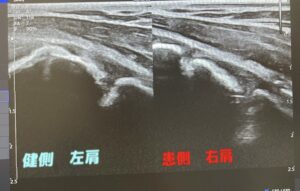

下記の写真がエコー写真↓

右側が左と違い骨が開いているのが確認できます。